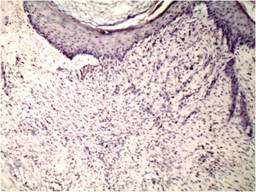

Histopatológicamente se apreciaron diferencias significativas en las muestras del grupo control con respecto a los grupos caso, entre ellas disminución de la fase aguda de la inflamación, aumento de la respuesta de inflamación crónica, incremento del grosor en el estrato córneo, aumento de vasos de neovascularización por campo y reacción granulomatosa en los grupos caso. La fibrosis fue muy similar en ambas muestras. Como se observa en las Tablas 3 y 4 las muestras de los pacientes con aplicación de PRPAA revelan datos de aceleración en el proceso de inflamación, de aguda a crónica con aumento de los vasos que nutren de la zona receptora al injerto, lo cual sugiere mayor adhesión y porcentaje de éxito en estos pacientes en comparación con los del grupo placebo (Tablas 3 y 4).

Hom et al.1 trataron biopsias experimentales con PPR en seres humanos y observaron un tiempo de cicatrización más rápido en comparación con el grupo control. Schade y Roukis16 observaron que la curación progresaba en pacientes con úlceras de pie diabético tratados con injerto cutáneo mallado, al igual que en nuestro estudio al aumentar el porcentaje de adhesión el tiempo de recuperación se acorta. Amable10 y Kaffashi17 encontraron resultados de recuperación clínica e histopatológicamente similares a los nuestros utilizando PRP alogénico (Figuras 2 y 3).

Figura 2: 4x, técnica HE, control. Se observa abundante inflamación aguda, infiltrado de neutrófilos intradérmicos y en dermis, edema, escasos vasos de neoformación.

Figura 3: 4x, técnica HE, caso. Epidermis con datos de queratinización, en dermis se observan abundantes vasos de neoformación y datos de reacción inflamatoria crónica.